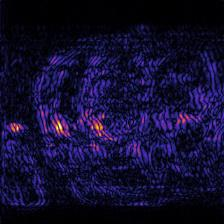

Recently, deep neural networks have greatly advanced undersampled Magnetic Resonance Image (MRI) reconstruction, wherein most studies follow the one-anatomy-one-network fashion, i.e., each expert network is trained and evaluated for a specific anatomy. Apart from inefficiency in training multiple independent models, such convention ignores the shared de-aliasing knowledge across various anatomies which can benefit each other. To explore the shared knowledge, one naive way is to combine all the data from various anatomies to train an all-round network. Unfortunately, despite the existence of the shared de-aliasing knowledge, we reveal that the exclusive knowledge across different anatomies can deteriorate specific reconstruction targets, yielding overall performance degradation. Observing this, in this study, we present a novel deep MRI reconstruction framework with both anatomy-shared and anatomy-specific parameterized learners, aiming to "seek common ground while reserving differences" across different anatomies.Particularly, the primary anatomy-shared learners are exposed to different anatomies to model flourishing shared knowledge, while the efficient anatomy-specific learners are trained with their target anatomy for exclusive knowledge. Four different implementations of anatomy-specific learners are presented and explored on the top of our framework in two MRI reconstruction networks. Comprehensive experiments on brain, knee and cardiac MRI datasets demonstrate that three of these learners are able to enhance reconstruction performance via multiple anatomy collaborative learning.